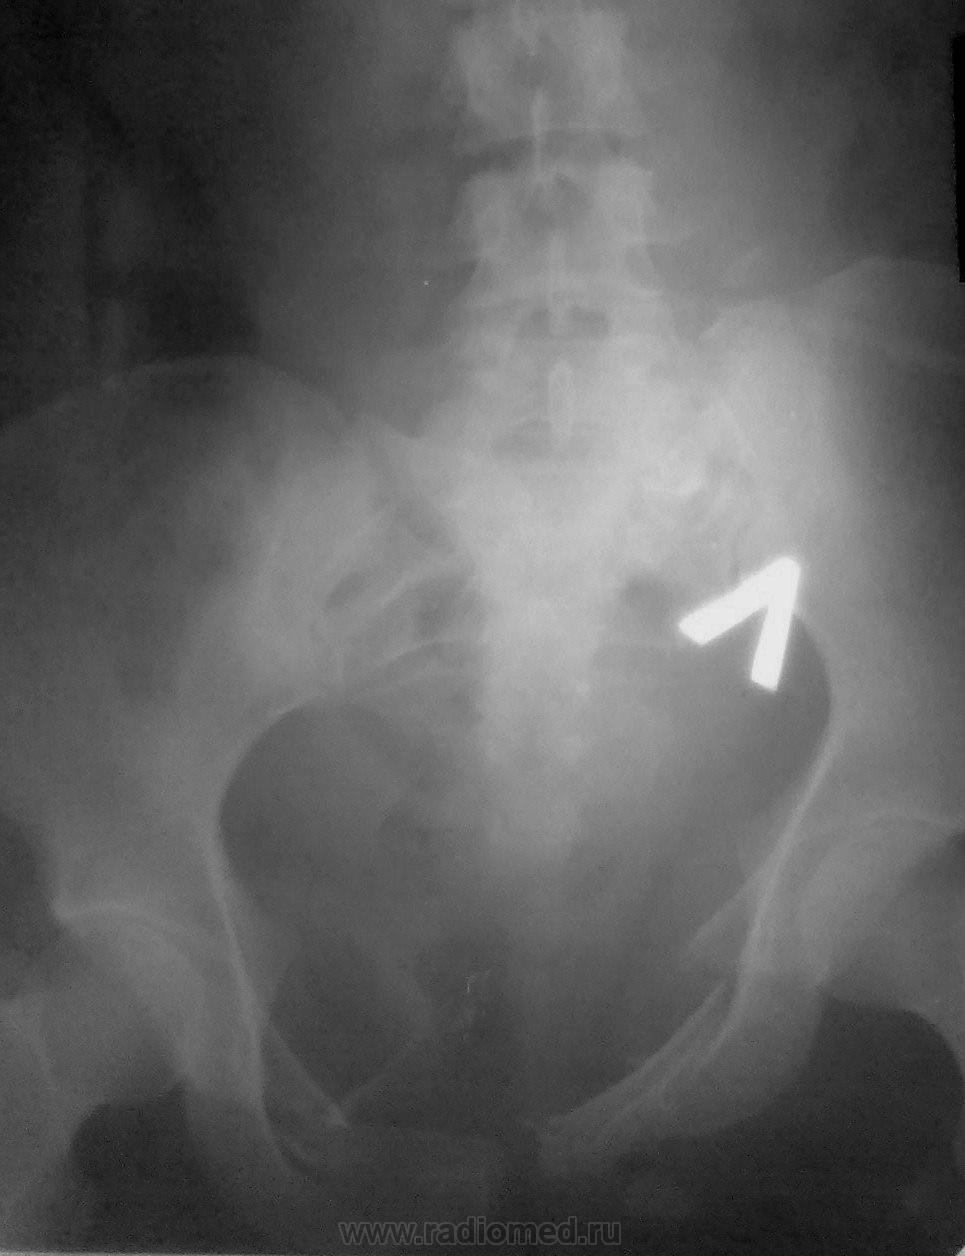

Случай 2.

Мужчина. ДТП, этим все сказано....ну и - всего много...

2. Оскольчатая бабочка + разрыв симфиза. С левой подвздошной в крыле - не совсем уверена. Удивительно, что мочевой цел... или ошибаюсь?

2. И крыло подвздошной, и левая половина крестца, и поперечный пятого поясничного - все так и есть... Да, на удивление, мочевой "удержал")))

А по крестцу - каша, не понять... Поперечный 4-го отлетел слева, а в поперечном 5-м видится асимметричная сакрализация. Крыло погнуто наверняка, но деталей не могу рассмотреть, наощупь всё). Мочевой - молодец, железный мочевой)).

А во втором случае - таз всмятку!

Случай №2. Перелом крестцовоподвздошного сочленения слева со смещением подвздошной кости. Двусторонний перелом лонных и седалищных костей, разрыв лонного сочленения.